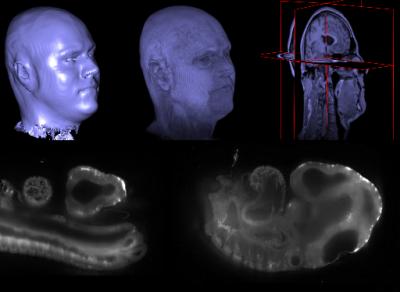

Ignacio Arganda, a young researcher from San Sebastián de los Reyes (Madrid) working for the Massachusetts Institute of Technology (MIT) is one of the driving forces behind Fiji, an open source platform that allows for application sharing as a way of improving biomedical-image processing. Arganda explains to SINC that Fiji, which has enjoyed the voluntary collaboration of some 20 developers from all over the world, has become a de facto standard that assists laboratories and microscope companies in their development of more precise products.

Ignacio Arganda is a postdoctoral researcher at the Laboratory of Computational Neuroscience of the Massachusetts Institute of Technology (MIT). Along with a group of researchers he implemented Fiji, a platform that allows for applications to be shared in order to improve and advance in the processing and analysis of biomedical imaging. "All of this in open source," outlines Arganda.

The scientists behind Fiji got in contact with Arganda because of his doctoral thesis. "I was working on a project involving the study of mammary gland development and breast cancer in mice and I had a few tissue samples. I began to develop a programme for elastic image alignment that would allow me to create a 3D reconstruction. They expressed their interest and called asking me to collaborate in the platform."

In the eyes of the researcher, this is an example of what lies within Fiji. Arganda now works on automatic learning systems aimed at recognising the edges of neurons from electronic microscope images in the MIT Laboratory of Computational Neuroscience. The developed applications have also been introduced into the platform.

Arganda is in charge of developing artificial intelligence programmes that automatically recognise neuron's edges and are then able to reconstruct wiring in the brain.